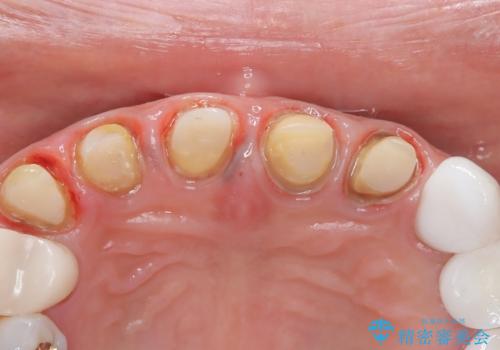

- 前歯の変色を主訴に来院されました。

歯茎のラインも整っていなかったため、手術を行いきれいな被せ物をいれることができました。

歯茎のラインを整える手術を行ったあとは、しばらく待ってから被せ物の治療を行っていきます。